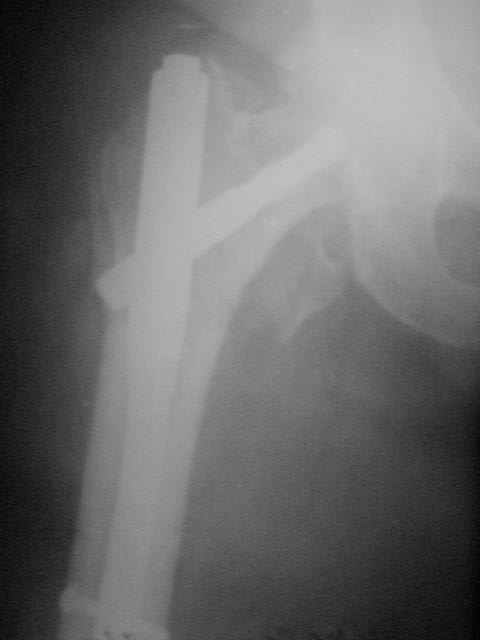

> Присоединяюсь. Хотя посмотреть бы вторую проекцию.

Согласен, вторую прекцию необходимо оценивать.

Боковая проекция нужна всегда, иногда послеоперационные снимки преподносят неожиданные сюрпризы:-(( даже при использовании ЭОПа интраоперационно.